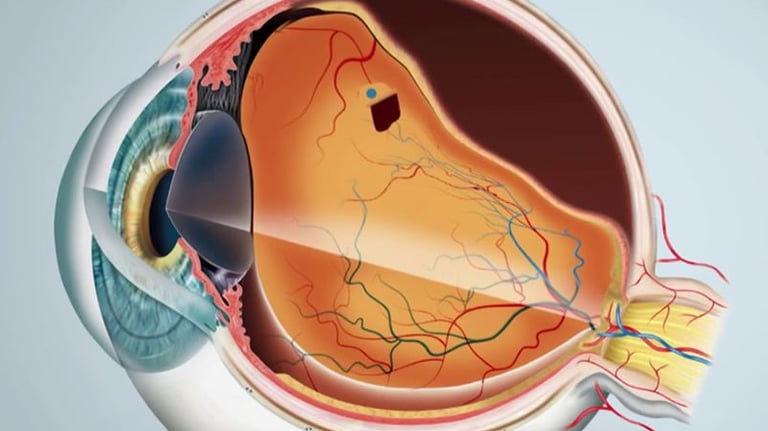

Retinopatia Diabética

Degeneração Macular Relacionada a Idade (DMRI)

Oclusões Vasculares da retina